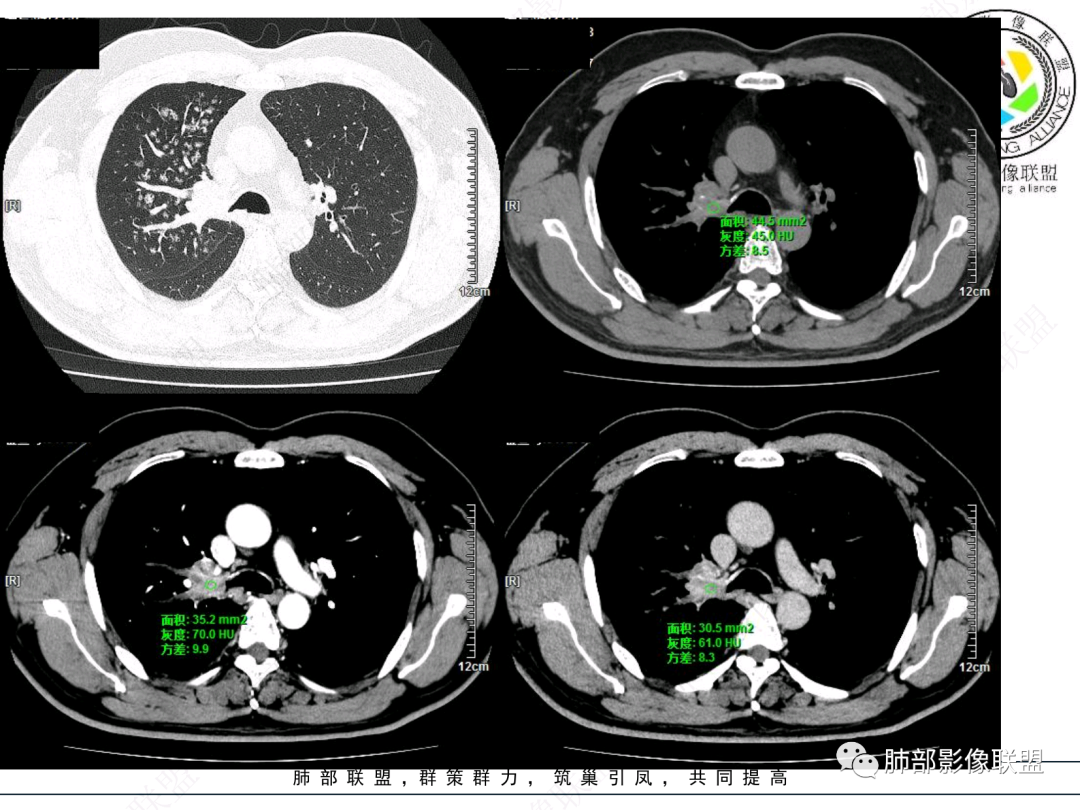

右肺上叶支气管截断,内见软组织密度结节,支气管管壁破坏,病变侵及管外,增强强化明显。右肺上叶沿气管血管束多发斑片影,考虑恶性性病变并阻塞性炎症,鳞癌,神经内分泌肿瘤。

男性,52岁,右侧主支气管腔内外占位伴点状钙化,病灶大部分位于腔外,右肺上叶散在结节影,气管腔内病灶,动脉期中度强化,静脉期强化减低,首先考虑气管腔内类癌可能,鉴别鳞癌,肺内病变倾向感染性病变;再有气管结核伴肺内播散。

男,52。间断咳嗽、咳痰2周,加重3天。胸部CT:右主、右上叶支气管多发软组织影,跳跃不连续,内可见小环状高密度,点状钙化,管壁破坏,上叶支气管堵塞,远端分支粘液栓,可见小支气管管壁增厚、管腔狭窄,沿支气管分布多发结节,无大片炎症不张。考虑:TB?NTM?鉴别Ca并阻塞性炎症。

腔内肿物,强化不均匀,强化程度为轻中度强化(CT值增加25HU),且强化特点为快进快出,右肺上叶支气管责任区域的阻塞性炎症加痰栓(气管镜也证实右上叶支气管内痰多)。这些均明确指向鳞癌。

这个病例比较好,我们的观察点在哪?这是右上叶支气管病变,需要了解:腔内、壁、腔外、远端,腔内有软组织密度影,近端膨隆。

红色:软骨连续性良好,壁外有软组织密度影,绿色:软骨不连续,破坏了,外面软组织密度影。

南边:提示软骨破坏,也就是病灶腔内朝壁外侵犯了——恶性。

远端支气管腔内不强化的是粘液栓,强化的是肿瘤。

如果在这种情况下临床想通过CT了解啥?主要是:a、与附近结构的关系:血管、淋巴结;b、远端情况;c、其他区域转移情况;

影像上分析的观察点:腔内、壁、腔外、远端,然后就是远端肺组织、淋巴结、肺血管、胸膜、其他肺部,这个人就是阻塞性炎症为主。